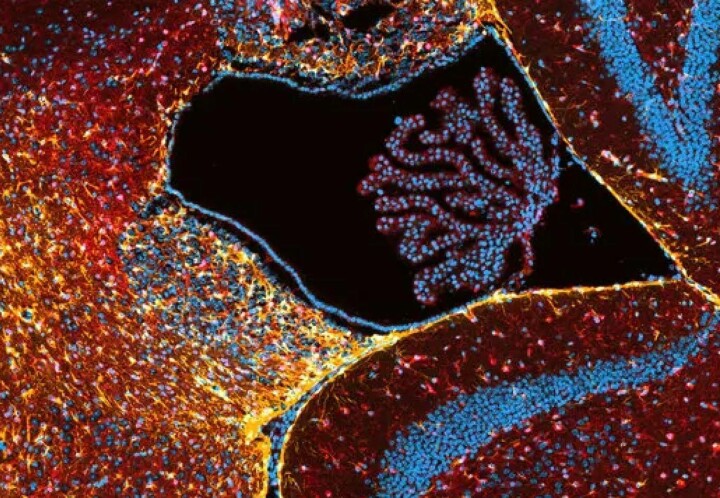

La nuova tecnologia cattura i dati in tre dimensioni e crea i cosiddetti “voxel”, cioè pixel in tre dimensioni, dove la dimensione di ciascun elemento costitutivo dell'immagine è di soli 5 micron. Questo, tra l'altro, può aiutarci a capire cosa succede nel cervello affetto dalla malattia di Alzheimer.

Con l'aiuto di un magnete da 9,4 Tesla, fino a tre o quattro volte più potente dei magneti odierni, e la potenza di calcolo di un supercomputer più piccolo, i ricercatori sono stati in grado di catturare una sequenza di immagini di un intero cervello di topo, di cui vediamo una sezione Qui.